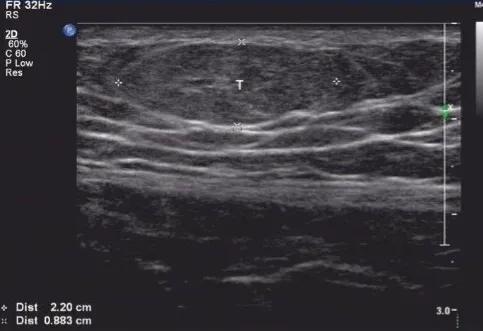

超声具有无放射性、操作方便且价格低廉等优势,是诊断脂肪瘤最为简便且准确的一种手段。脂肪瘤切面呈扁圆形,长轴与皮肤平行,绝大多数边缘清晰,有完整的包膜回声。脂肪瘤内部的回声常与脂肪相近,也可表现为强回声、低回声或混合回声。脂肪瘤的质地通常柔软,加压探头时会产生变形。

脂肪瘤表现为皮下脂肪层内混合回声的实性团块与周围脂肪组织分界清晰